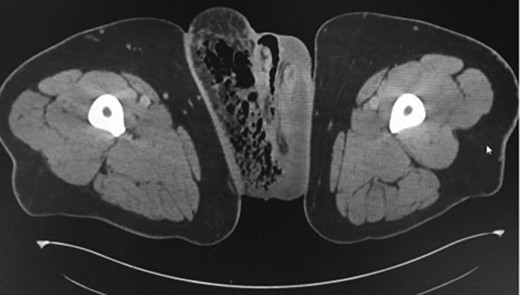

A 45-year-old male, with a background of type 2 diabetes mellitus and morbid obesity (BMI 40.9) presented septic to the Emergency Department, with a one-week history of increasing scrotal pain, penile discomfort, and difficulty ambulating. He was febrile and tachycardic on presentation. Physical examination revealed a grossly swollen and oedematous scrotum with tissue necrosis evident over the right posterior hemiscrotum. Erythema and induration extended to the rectum, pubic and right inguinal regions. Biochemistry revealed a polymorphonuclear leucocytosis, hyperglycaemia and lactic acidosis. A computed tomography scan of his abdomen/pelvis confirmed a markedly oedematous right hemiscrotum with extensive subcutaneous emphysema tracking into the right inguinal region and anterior abdominal wall (Figs 1 and 2).

Coronal CT scans of abdominopelvic region demonstrating gas and in the right groin region.